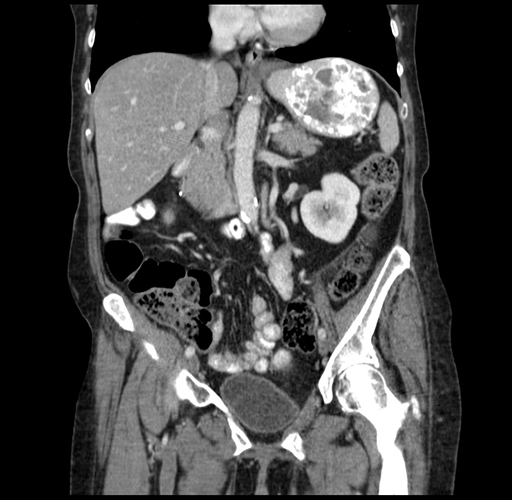

Pre-Chemo: Coronal Venous

Coronal Venous